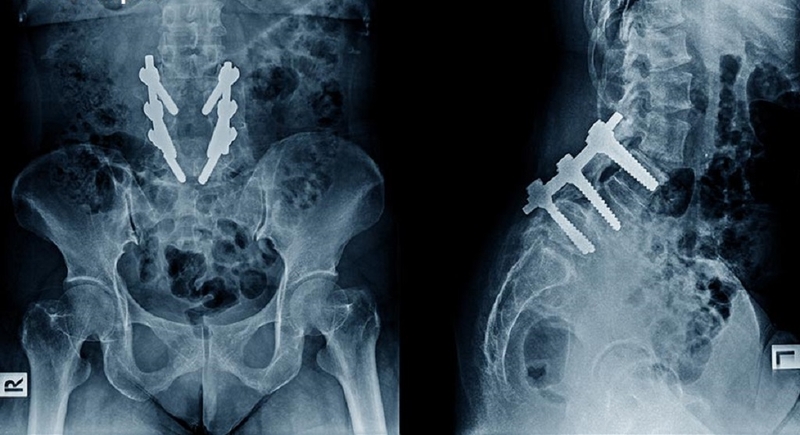

• Ghép xương: Mảnh xương thay thế được cố định vào vị trí cần ghép bằng các thiết bị như đinh ghim, đĩa, ốc vít, dây, cáp hoặc các kỹ thuật khác. Mục tiêu là đảm bảo rằng xương ghép vừa vặn hoàn hảo và ổn định trong quá trình phục hồi.

Ghép xương: Phương pháp khôi phục và tái tạo xương sau chấn thương 2

Mảnh xương thay thế được chuẩn bị với kích thước và hình dạng phù hợp với vùng cần ghép